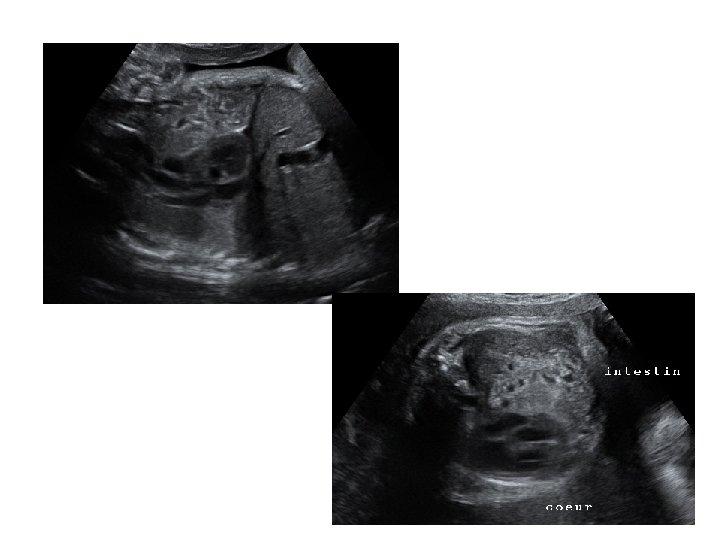

- thorax : cœur (position, 4 cavités équilibrées, septum inter ventriculaire, croisement Ao/AP), poumons - abdomen : paroi intègre, estomac (position, volume), vésicule biliaire, intestin grêle - arbre urinaire : vessie (position, volume), 2 reins - sexe - rachis avec son revêtement cutané - membres : 4 x 3 segments, 5 doigts aux 2 mains, mouvements d’ouverture des mains, mesure du pied

• Étudier les annexes fœtales - cordon: 2 artères, 1 veine - placenta : épaisseur et niveau d’insertion - liquide amniotique : volume.